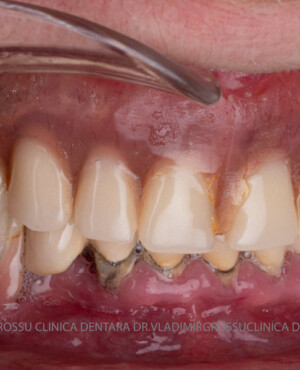

Caz 2